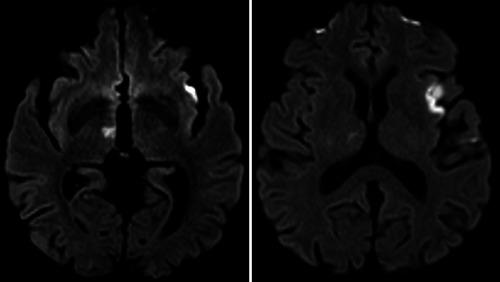

Of 5022 consecutive patients with AIS, 870 underwent EVT. Seven patients (0.8%) had EVT following cardiac surgery. Operations varied: two coronary artery bypass grafting (CABG), two transcatheter AVR, one redo surgical aortic valve replacement (AVR), one mitral valve repair and one patient with combined aortic and mitral valve replacements and CABG. Meantime postsurgery to stroke symptoms onset was 3 days (range 0-9 days). Median NIHSS was 26 (range 10-32). Five patients had middle cerebral artery occlusion and two internal carotid artery (n = 2). Median time between onset of symptoms and recanalization was 157 min (range 97-263). Two patients received Intra-arterial Thrombolysis. All patients survived and were discharged to another hospital (n = 3), home (n = 2), or rehabilitation facility (n = 2). Median 3-month mRS was 3 (range 0-6).

在 5022 例连续 AIS 患者中,870 例行 EVT。7 例(0.8%)在心脏手术后行 EVT。手术类型多样:2 例冠状动脉旁路移植术(CABG)、2 例经导管主动脉瓣置换术(AVR)、1 例再次外科主动脉瓣置换术(AVR)、1 例二尖瓣修复术和 1 例主动脉瓣和二尖瓣置换术联合 CABG。同时,术后至卒中症状发作时间为 3 天(范围 0-9 天)。NIHSS 中位数为 26(范围 10-32)。5 例患者大脑中动脉闭塞,2 例颈内动脉闭塞(n=2)。症状发作至再通的中位时间为 157 分钟(范围 97-263)。2 例患者接受了动脉内溶栓治疗。所有患者均存活并出院至另一家医院(n=3)、家中(n=2)或康复设施(n=2)。中位 3 个月 mRS 为 3(范围 0-6)。